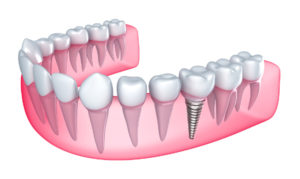

طرق زراعة الأسنان بالصور

قد يكون مصطلح زراعة الأسنان مخيفا للبعض، لكنه بفضل التكنولوجيا المتقدمة في مجال طب الأسنان لم يعد أمرا صعبا على الأطلاق.

زراعة الأسنان التقليدية تجهيز عظام الفك :

و في هذه طريقة زراعة الأسنان يقوم الطبيب بإزالة الأسنان المريضة، مما يتطلب قضاء فترة من الوقت تصل إلى ثلاثة شهور.

وذلك لإلئام عظام الفك بعد هذه العملية وتكون الخطوة الثانية هي زراعة جذر تيتانيوم في عظام الفك، ويكون هذا الجذر بمثابة دعامة لسن أو لعدة أسنان صناعية.

وضع الأسنان الصناعية بعد زراعة جذر التيتانيوم، وأثناء التئام عظام الفك من هذه العملية، توضع للمريض إحدى أنواع الأسنان الصناعية.

زراعة الأسنان الفورية

تستخدم هذه الطريقة عندما يكون الفراغ المخلف من خلع الأسنان المريضة أصغر من حجم المعهود من الأسنان المزروعة.

وفي هذه الحالة، يمكن للسن المرزوع أن يلتحم مع الأسنان الأصلية في منطقة السن المزال، ويكون دائم الثبات.

وضع الأسنان الصناعية عند وضع أكثر من جذر، ويكون ذا ثبات جيد في يوم التركيب، يمكن في هذه الحالة وضع جسر مؤقت.